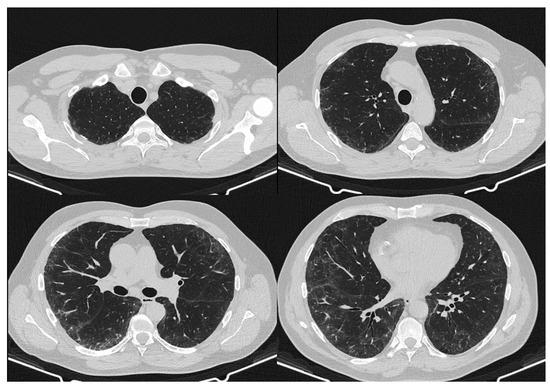

2. Case Report